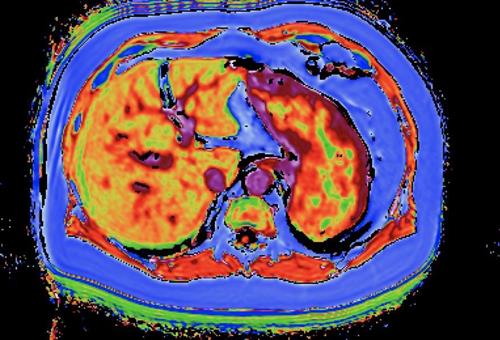

MRI imaging of fibrotic and fatty liver |